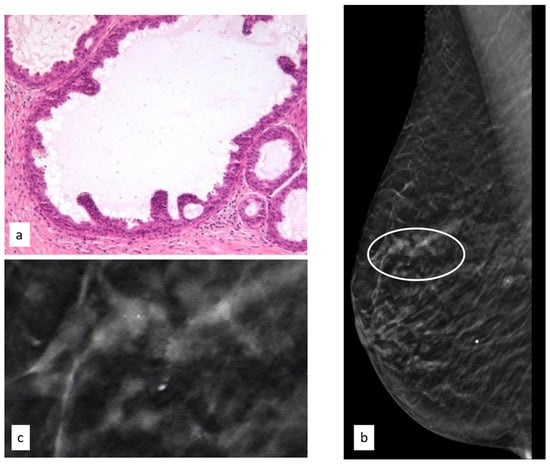

3.3.3. Lobular Intraepithelial Neoplasia

In total, 186 women had an initial diagnosis of LIN (25.4%), and the median age of this group was 52.7 years (range 33.7–83.5 years).

The initial radiological findings were 111 microcalcifications, 68 masses, and seven architectural distortions; the mean radiological suspicion level was BIRADS 4 (range 2–5). Illustrative radiologic and histologic examples of LIN are shown in Figure 5.

Figure 5.

Histologic picture (a, Magnification (×20)) and radiological presentation ((b) right CC view; (c) magnification) of lobular intraepithelial neoplasia (white circle).

Of the 186 LIN patients, 17 (8.8%) developed subsequent breast cancer during follow-up, 11 (64.7%) in the same breast as the LIN and 6 (35.3%) in the contralateral breast.

The median time interval from first diagnosis of a B3 lesion to subsequent diagnosis of BC was 50.6 months.

3.3.6. Radial Scar

In total, 103 women had an initial diagnosis of RSs (14%), and the median age of this group was 47.9 years (range 24.9–81.7 years).

The initial radiological findings were three microcalcifications, 58 masses, and 42 architectural distortions; the mean radiological suspicion level was BIRADS 4 (range 2–5). Illustrative radiologic and histologic examples of RSs are shown in Figure 8.

Figure 8.

Histologic picture (a, Magnification (×10)) and radiological presentation ((b) right CC view; (c) magnification) of a radial scar (white circle).

Of the 103 RS patients, 4 (3.9%) developed subsequent breast cancer during follow-up after a median time interval of 73.9 months. In three cases (75%) the cancer was found in the same breast as the RS, and in one case (25%) it was found in the contralateral breast.